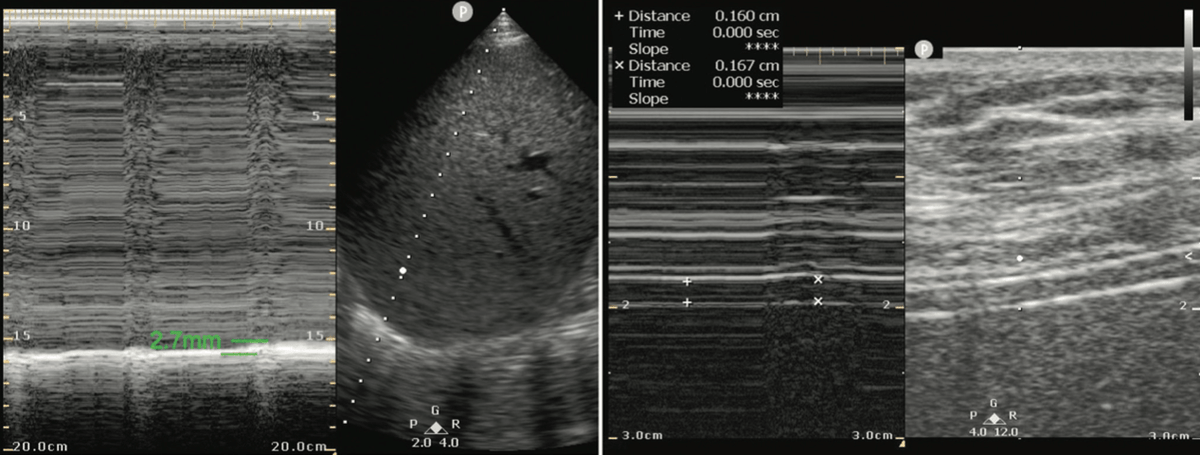

Your 89-year-old female patient is improving after her initial admission to the ICU for respiratory failure due to pneumonia. She is alert and normotensive and signals her desire to be removed from the ventilator. On her spontaneous breathing trial, you perform this thoracic US:

She is likely to fail weaning. The patient has evidence of diaphragmatic dysfunction (DD) on thoracic ultrasound. In a recent meta-analysis, this was associated with a sensitivity of 85% and 8.8 odds ratio of spontaneous breathing trial failure as opposed to those without DD.

DD is assessed by measuring the diaphragmatic excursion (DE) and the diaphragmatic thickening fraction (DTF). [*eds: not our abbreviation]. For DE, place a low-frequency transducer in the mid to post-axillary line with the indicator pointed cephalad, similar to a FAST window.

Place the M-mode line at the juncture of the diaphragm and vertebral column or the costal-diaphragmatic junction. The tracing will reveal peaks with the amplitude of the peaks directly related to the inferior displacement of the diaphragm.

A DE value of ≤10-15 mm for normal spontaneous breathing and <25 mm for maximal inspiratory effort is considered abnormal. The figure below shows normal diaphragmatic excursion using M-mode.

Our patient had a DTF of 4.4% and DE of 2.7 mm, so there is clear diaphragmatic dysfunction.

Learning Point: A DE value of ≤10-15 mm for normal spontaneous breathing and <25 mm for maximal inspiratory effort, or DTF < 30%, is associated with diaphragmatic dysfunction.